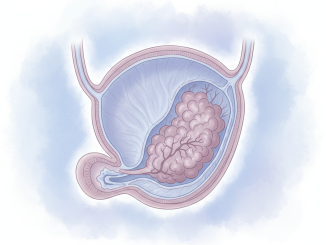

یک سامانه جدید دارورسانی هدفمند به نام TAR-200 در یک کارآزمایی بالینی فاز ۲ نتایج چشمگیری نشان داده است؛ این روش موفق شد در ۸۲٪ از بیماران مبتلا به سرطان مثانه غیرعضلهای پرخطر که به […]